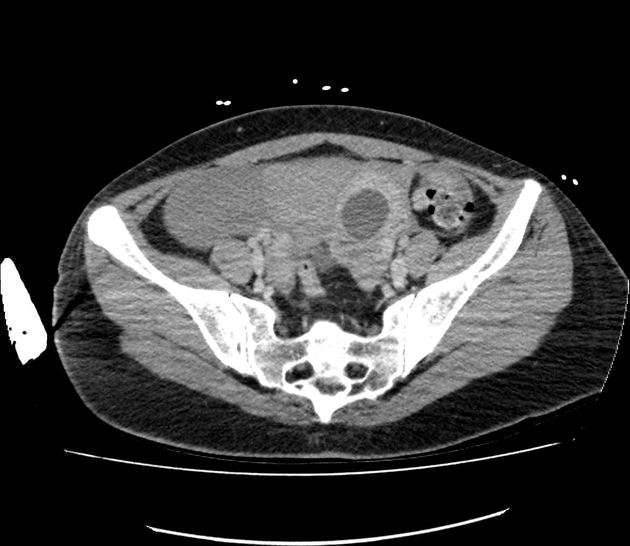

خطوة أخرى للتشخيص هي الموجات فوق الصوتية عبر المهبل. يتضمن ذلك إدخال أداة تشبه العصا الخاصة في المهبل حتى يتمكن طبيبك من معرفة ما إذا كان كيس الحمل في الرحم.

قد يستخدم طبيبك أيضًا فحص دم لتحديد مستويات هرمون النمو (hCG) والبروجستيرون، هذه هرمونات موجودة أثناء الحمل. إذا بدأت مستويات الهرمون في الانخفاض أو بقيت كما هي على مدار بضعة أيام ولم يكن كيس الحمل موجودًا في الموجات فوق الصوتية، فمن المحتمل أن يكون الحمل خارج الرحم.

إذا كنت تعاني من أعراض حادة مثل الألم الشديد أو النزيف، فقد لا يكون هناك ما يكفي من الوقت لإكمال كل هذه الخطوات. يمكن أن تمزق قناة فالوب في الحالات القصوى، مما تسبب في نزيف داخلي حاد. سيقوم طبيبك بعد ذلك بإجراء عملية جراحية طارئة لتوفير علاج فوري.